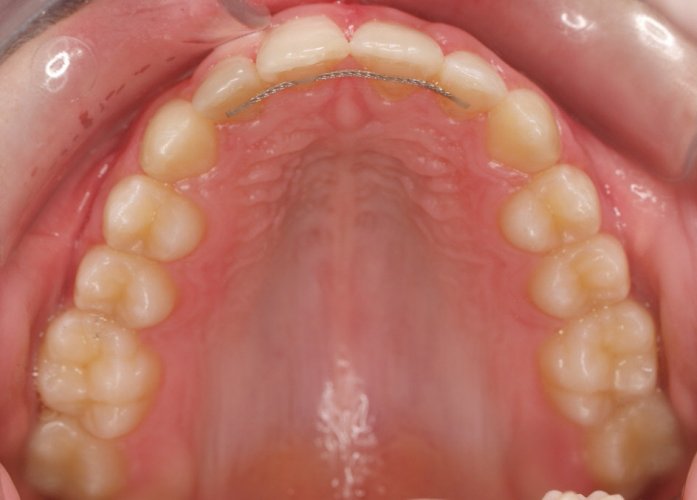

El paciente A.J. de 11 años, acude a nuestra consulta con apiñamiento maxilar importante. El canino lateral (12) está en mordida cruzada. Presenta una Clase II molar y canina, y la línea media está desviada. Se realizó un tratamiento con brackets autoligables metálicos de smartclip 022. La duración del tratamiento fue de 22 meses.

El paciente actualmente ha terminado el tratamiento con brackets y lleva una contención fija de 2-2 en maxilar y 3-3 en mandibular; para complementar también lleva una férula ESSIX durante la noche.

INICIO FINAL